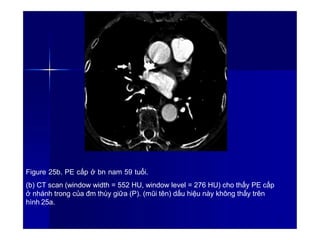

Figure 25a. PE cấp ở bn nam 59 tuổi.

(a) CT scan (window width = 400 HU, window level = 40 HU) cho thấy huyết

khối ở đm liên thùy (P) (mũi tên).

Figure 25b. PE cấp ở bn nam 59 tuổi.

(b) CT scan (window width = 552 HU, window level = 276 HU) cho thấy PE cấp

ở nhánh trong của đm thùy giữa (P). (mũi tên) dấu hiệu này không thấy trên

hình 25a.